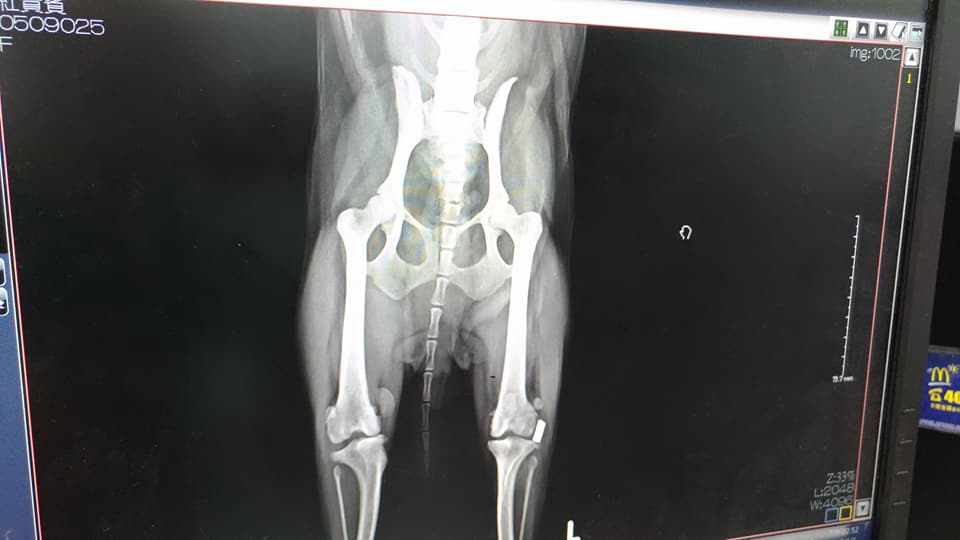

主題: 繁殖場丟出,後雙腿變形開刀治療的葳葳(右後腿手術費用) 申請者姓名: 臺北市支持流浪貓絕育計劃協會 花色: 申請日期: 2017-11-16 10:28:31 申請者部落格: 申請者臉書網址: 所在縣市/合作醫院: 台北市/沐恩動物醫院 治療費用: 51400元 需求人數: 53人 已結案 (2024-06-01 13:20:10) 報名人員: Karina Hsiao(已付款)、beforn(已付款)、Warm Sun(已付款)、Jane(已付款)、Hsu(已付款)、心桓(已付款)、sywn(已付款)、Kitty Chen(已付款)、Tracy Kao x2(已付款)、Shane(已付款)、Mason Mei(已付款)、Sean Wu x5(已付款)、Nicole Chen(已付款)、小瓜(已付款)、Coffeemilk(已付款)、Joyce Chen x3(已付款)、chiawei(已付款)、張宇徹(已付款)、Sunny(已付款)、Patricia Lin x2(已付款)、charlene(已付款)、Eli Hsiao(已付款)、Mf x2(已付款)、ShenJang Fann x2(已付款)、Ruting Xiao(已付款)、Peggy Lin(已付款)、詹惠如(已付款)、孫小姐一家、Fan(已付款)、Ivy(已付款)、東爵模特兒(已付款)、謝沛豈 x2(已付款)、Jasmine Lin(已付款)、嘎嘎(已付款)、孫小姐一家(已付款)、陳湘澐(已付款)、家有三色喵、TC(已付款)、SY(已付款)、Bella Chen(已付款)、Kim Meng(已付款)、可樂(已付款)、Hui Hui Ting x2(已付款)、 候補人員: 動物病情說明: 葳葳原先是隻種母,從收容所救出時,

而由於葳葳的雙後腿嚴重變形無力,若不開刀治療

未來不久後可能無法行走,甚至產生後續更多的醫療花費

葳葳雙腳的手術分別訂於4/27以及8/19

今日葳葳照X光,看術後膝蓋骨的復原狀況,X光片顯示,復原狀況還不錯,膝蓋骨有長在正確的地方。